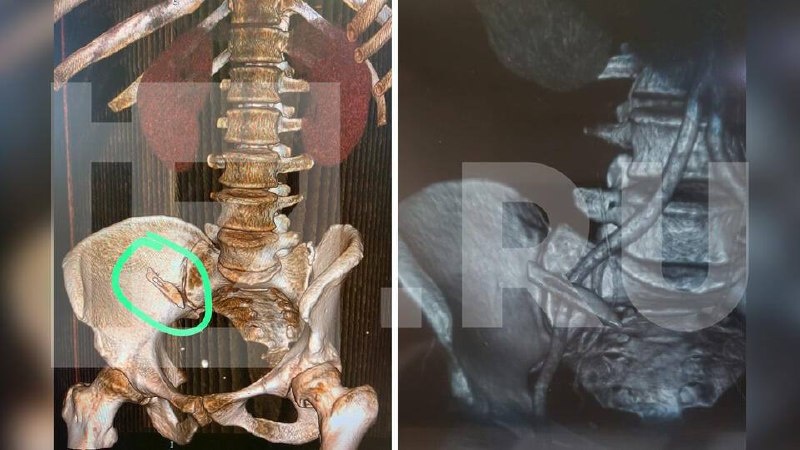

Как рассказала «РЕН-ТВ» пациентка, в январе 2023 года ей диагностировали онкологию на поздней стадии. Врачи провели операцию по удалению опухоли кишечника. Спустя несколько месяцев после хирургического лечения она направилась в Екатеринбург для прохождения курса химиотерапии. На компьютерной томографии в брюшной полости обнаружили скальпель, который вплотную прилегал к артерии.

Чтобы вы понимали, на фото действительно скальпель.